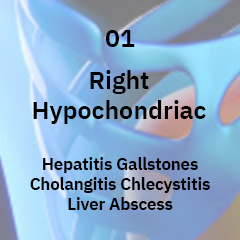

Bacterial liver abscess occurs because of various other infections in the digestive tract like appendicitis, stones in the bile duct or sometimes even an infected by piles or fistula.

The gallbladder is a small sac located on the right-hand side of the body, on the underside of the liver, below the front rib cage.Its main purpose is to collect and concentrate a digestive liquid (bile) produced by the liver.